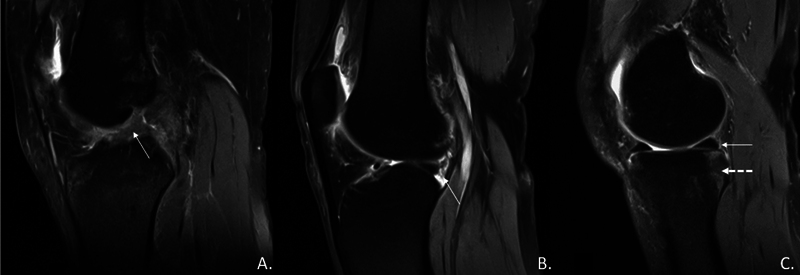

半月板撕裂,尤其是内侧半月板撕裂,在前交叉韧带(ACL)损伤中很常见。修复的前内侧门静脉(RAMP)病变,与前交叉韧带破裂相关的特定半月板损伤,影响内侧半月板后角的外周附着。虽然股骨滑车形态与前交叉韧带撕裂之间的关系已被确立,但其与RAMP病变的关系仍未被探讨。本研究利用磁共振成像(MRI)研究了acl缺失膝的股骨滑车形态与RAMP病变之间的关系,并评估了MRI与关节镜检查的准确性。材料和方法本研究在一家三级医疗中心进行了为期18个月的横断面观察性研究。该研究包括126名接受关节镜下前交叉韧带重建和术前MRI检查的成年患者。变量包括年龄、性别、体重指数、创伤性质和各种MRI参数,包括股骨滑车形态和RAMP病变的存在。将MRI检查结果与关节镜检查结果进行比较以评估诊断的准确性。结果MRI检查21例(16.7%),关节镜检查28例(22.2%)。MRI检测RAMP病变的敏感性为71.4%,特异性为99.0%。股骨滑车形态与RAMP病变无明显关联。然而,胫骨内侧斜坡(TS)和胫骨后内侧骨水肿(PMTBE)与RAMP病变显著相关。MRI与关节镜检查的一致性较高(Cohen’s kappa = 0.773, p)。结论本研究发现,acl缺失膝的股骨滑车形态与RAMP病变无显著相关性。相反,内侧TS和PMTBE是显著的预测因子。与关节镜检查相比,MRI具有高特异性,但敏感性中等。

Introduction  Meniscal tears, especially in the medial meniscus, are common in anterior cruciate ligament (ACL) injuries. Repaired anterior medial portal (RAMP) lesions, specific meniscal injuries associated with ACL ruptures, affect the peripheral attachment of the posterior horn of the medial meniscus. While the relationship between femoral trochlear morphology and ACL tears is established, its association with RAMP lesions remains unexplored. This study investigates the association between femoral trochlear morphology and RAMP lesions in ACL-deficient knees using magnetic resonance imaging (MRI) and evaluates MRI's accuracy against arthroscopy. Materials and Methods  This hospital-based, cross-sectional observational study was conducted in a tertiary care center over 18 months. It included 126 adult patients who underwent arthroscopic ACL reconstruction and had preoperative MRI. Variables included age, gender, body mass index, trauma nature, and various MRI parameters, including femoral trochlear morphology and presence of RAMP lesions. MRI findings were compared to arthroscopic findings to evaluate diagnostic accuracy. Results  RAMP lesions were detected in 21 participants (16.7%) via MRI and 28 participants (22.2%) via arthroscopy. MRI showed 71.4% sensitivity and 99.0% specificity for detecting RAMP lesions. No significant association was found between femoral trochlear morphology and RAMP lesions. However, medial tibial slope (TS) and posterior medial tibial bone edema (PMTBE) were significantly associated with RAMP lesions. The agreement between MRI and arthroscopy was high (Cohen's kappa = 0.773, p  < 0.001). Conclusion  This study found no significant association between femoral trochlear morphology and RAMP lesions in ACL-deficient knees. Instead, medial TS and PMTBE were significant predictors. MRI proved to have high specificity but moderate sensitivity compared to arthroscopy.